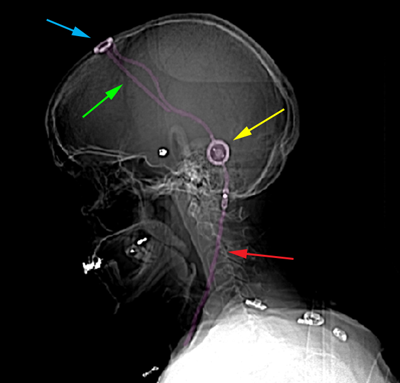

Σύστημα κοιλιοπεριτοναϊκής παροχέτευσης με βαλβίδα. Κοιλιακός καθετήρας (εισέρχεται στο κοιλιακό σύστημα του εγκεφάλου) με πράσινο βέλος, ρεζερβουάρ Ε.Ν.Υ. με κυανό βέλος, βαλβίδα ρύθμισης της πίεσης με κίτρινο βέλος, περιτοναϊκός καθετήρας με κόκκινο βέλος. |